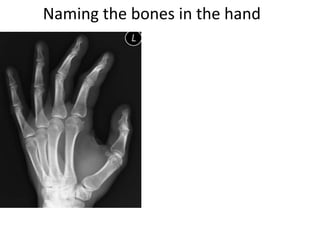

- Naming the bones, joints, tendons, nerves and skin landmarks of the hand and wrist.